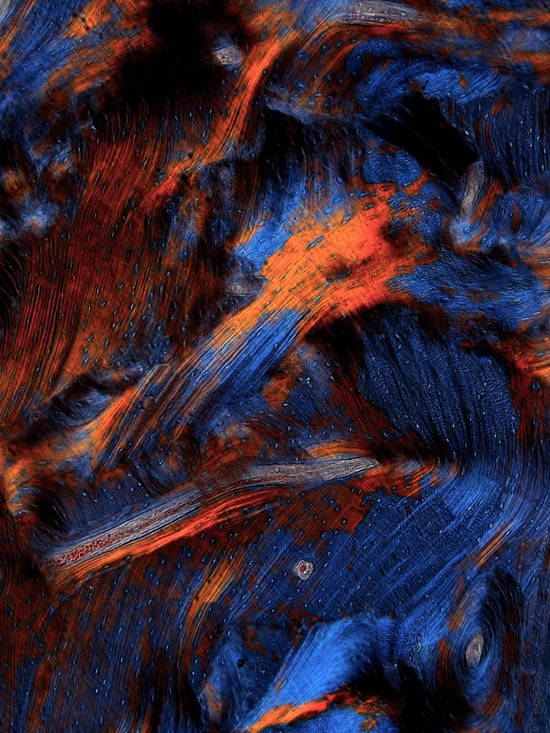

毫无疑问,第一大看点,当属书中收录的85幅显微摄影作品。单看五个章节的标题,就足以想象作品之意境。

作者试图通过给生物学和医学带来巨大革命的显微镜,去探寻生命的“无穷之境”。本书看似一本艺术画册,但其展示的“风景”却来自人体的组织和细胞,来自一位经常与“生和死”打交道的病理医生的独特视角。它可引发人们对宏观“大宇宙”和人体“小宇宙”的哲学思考,感叹和领悟中华文化中有关“天人合一、道法自然”的深刻内涵。

《星空》

脱钙骨组织切片和封片胶,X100,偏振光,2017

脱钙骨组织切片,X100,偏振光,2019

骨组织脱钙切片X100,明视野+偏振光,2019